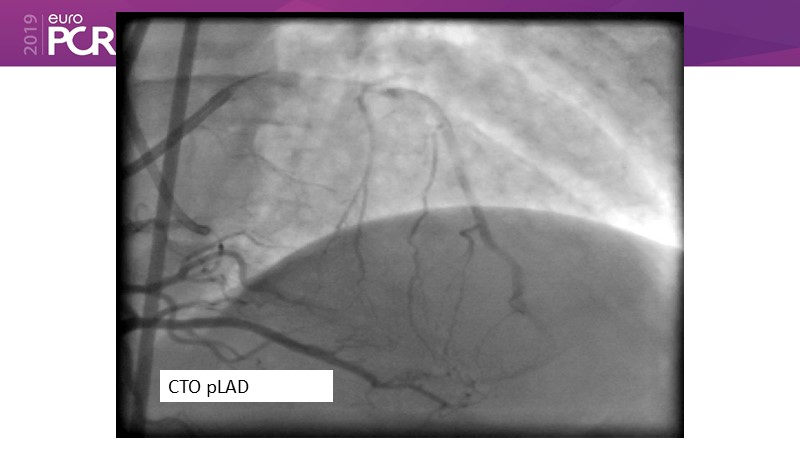

Consult this session to learn about the DCB-only concept, treatment methodology and consensus group recommendations, and discover the latest scientific evidence of DCB-only in de novo lesions and in complex PCIs.